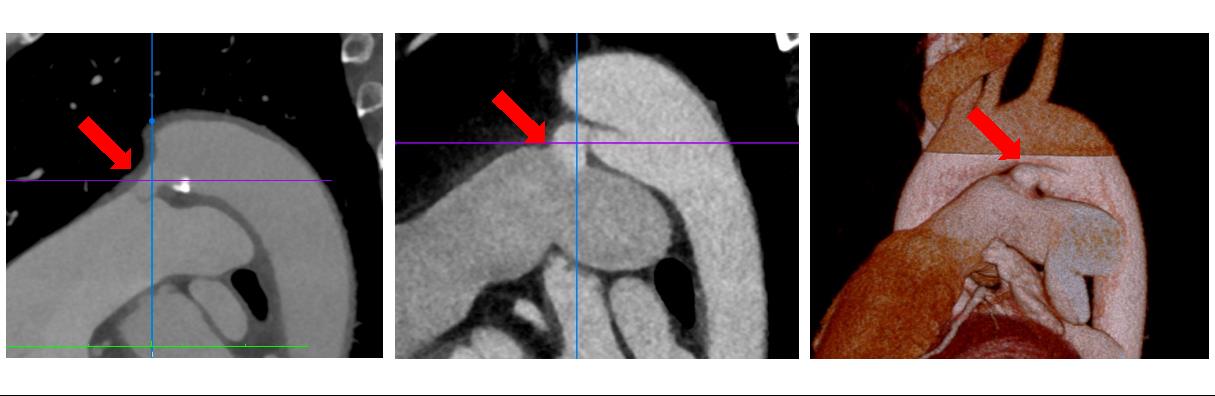

当院では、特に成人先天性心疾患(ACHD:Adult congenital heart disease)の方の診断、治療、手術に取り組んでいます